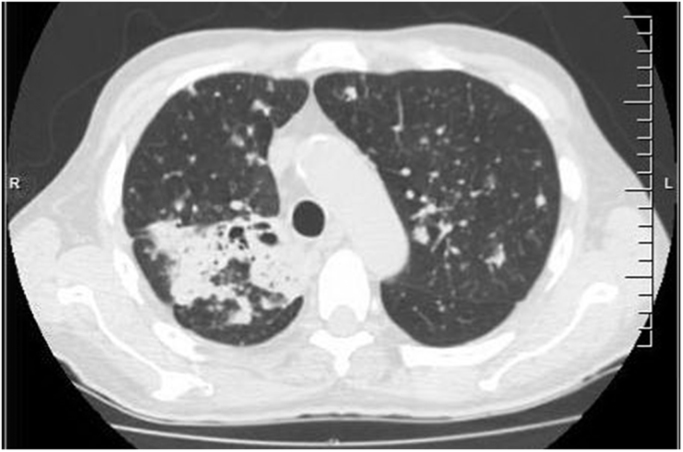

A repeat CT scan of the chest obtained day 26 which was three weeks after the initiation of itraconazole demonstrated cavitation with bronchial dilatation within the previously demonstrated confluent consolidation within the right upper lobe (Fig. 3).

Fig. 3.

Follow up CT of the chest (IRIS).

The left upper lobe lesion was surprisingly slightly larger in size with interval progression in the size and number of innumerable pulmonary nodules, several of which were cavitating. The patient however was afebrile and clinically improved with no respiratory complaints. A repeat bronchoscopy performed day 40 demonstrated mucopurulence in left lung. Bacterial, fungal, acid-fast bacilli, and Legionella cultures of the BAL fluid were negative. The BAL fluid galactomannan, pneumocystis PCR, and the respiratory viral panel PCR were also negative. Additionally, an itraconazole trough serum level was obtained on day 47 and was found to be 1.6 µg/mL, well within the therapeutic range. The patient continued to make an unremarkable recovery, thereafter.

The unique features of our case includes the positive BAL fluid galactomannan derived from the cross reactivity of the polysaccharide contained on both Blastomyces dermatididis and Histoplasma capsulatum [5] along with the positive urine Histoplasma antigen [6]. In addition, the worsening of his pulmonary findings at the time of his repeat CT scan of the chest three weeks after the initiation of therapy was also not in keeping with his marked clinical improvement. These findings may have been representative of the immune reconstitution inflammatory syndrome (IRIS) although alternative hypotheses could have been entertained for his worsening imaging findings (suboptimal therapeutic drug levels of itraconazole and a new possible superimposed infection) [7]. Regarding the therapeutic drug levels, the itraconazole trough level was assayed and found to be appropriate (1.6 µg/mL, range > 1.0 µg/mL for systemic infection). As for a new possible superimposed infection, the repeat bronchoaveolar lavage was unremarkable. Therefore, it was felt that the worsening CT chest findings were consistent with IRIS.